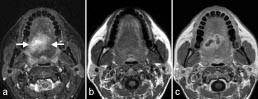

Selv om MR-teknikken kan fremstille samme anatomi med mange ulike bildekontraster, finnes det likevel patologiske prosesser med vevsegenskaper (f.eks. protontetthet, T1- og T2-verdi) som er så lik omgivende normalt vev at de derfor vanskelig lar seg detektere. Tilførsel av kontrastmiddel kan øke deteksjonen og også bidra til å karakterisere en lesjon. Det finnes mange ulike kontrastmidler for MR, men felles for de aller fleste er at de forkorter T1- og T2-relaksasjonen til omgivende protoner. Kontrastmidler som forkorter T1, fører til økt signal på T1-vektede bilder (positive kontrastmidler) (fig 9), mens kontrastmidler som forkorter T2, gir redusert signal på T2-vektede bilder (negative kontrastmidler).